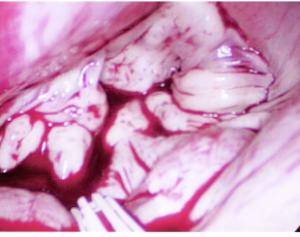

Dr. Glower took "before and after" pictures of my valve, which were shown to me in ICU. Below are those pictures.

Mitral Valve Prolapse Picture - Before

Mitral Valve Before Surgery

Apparently, my valve was almost twice the size as normal, but was still repairable with apparently neglible leakage. The first picture (above), shows the valve prior to surgery. I don't know what it is supposed to look like, but it doesn't look anything like a valve that would work property. Both the anterior and posterior leaflets look like a jumbled mess. The lower picture shows the post-repair state of the valve. You can clearly see the annular ring put in place to resize and support the valve structure. The reconstructed anterior leaflet is clearly visible, where the posterior leaflet is visible to the right and bottom left.